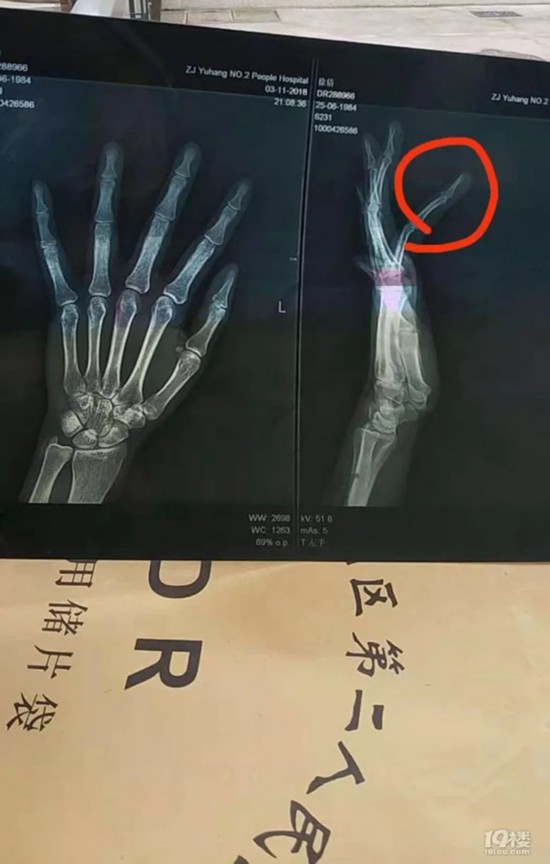

当天晚上,徐女士去了医院,拍了片子,她的无名指骨折了,全身多处挫伤。

徐女士说,医生说她的手指即使好了,也可能畸形,丧失部分功能。